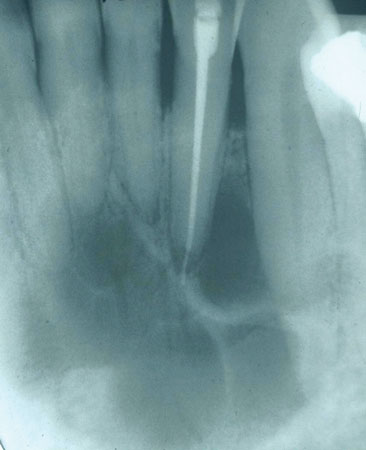

vanligtvis upptäckt genom en röntgenbild som visar en radiolucent lesion av underkäken eller maxilla, står CGCG för färre än 7% av alla godartade tumörer i käftarna-med en prevalens för underkäken med en hastighet på 65 till 75% och påverkar kvinnor oftare än män. Tillväxten är en intraosseös lesion bestående av cellulär fibrös vävnad (fibroblaster) som innehåller multinukleära jätteceller. CGCG växer mycket långsamt. Men när den ses i en mer aggressiv form uppvisar den snabb tillväxt, svullnad, lossning av tänderna, förskjutning av tänderna och det tränger in i kortikalbenet (se Figur 1).

Figur 1

radiografiska egenskaper: CGCG ses som en multilokulär lesion eller, i sällsynta fall, en unilokulär lesion som har väldefinierade marginaler. Gränserna kan ha ett skulpterat utseende. Den mer aggressiva formen kan skildra inte bara rotresorption utan också perforering av kortikalt ben.

Perioral och intraoral egenskaper: CGCG är vanligtvis smärtfri om inte storleken och expansionen av lesionen blir överdriven. Finns främst anterior till den första molära, radiografiska framträdanden kan noteras på grund av divergensen och expanderande marginaler av en radiolucent lesion. Förlust av lamina dura kan vara en tidig indikation. Smärta tillsammans med ett noterat kliniskt utseende ses vanligtvis när lesionen tränger igenom och sticker ut genom det kortikala benet, men rapporteras inte initialt. CGCG kan då noteras som en mjukvävnad, plattbaserad nodul med en blå-till-lila färg när detta utvecklingsstadium erhålls.